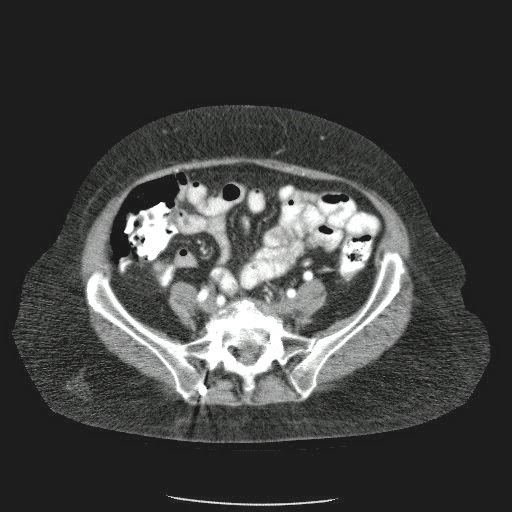

- ¿Hallazgos Escanografia?

2. Hay una colección de la pared abdominal en el flanco derecho, que realza en la periferia con el contraste, e intraabdominal tiene aire pero no me parece colección intraabdominal porque la grasa no está alterada.

3. Recomendado: Drs. JOSÉ M. ZUÑIGA A.1, FRANCO ORELLANA G.1, MARCELO CASTRO S.3, ROLANDO SEPÚLVEDA D.4, HORACIO RÍOS R.4, Int. VELIA SALDÍAS H.2. Neumatosis Intestinal: Caso Clínico-Radiológico. Pneumatosis intestinalis. A case report. Rev Chil Cir v.61 n.1 Santiago feb. 2009